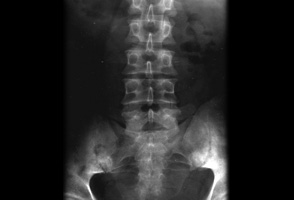

- pelvic x-ray